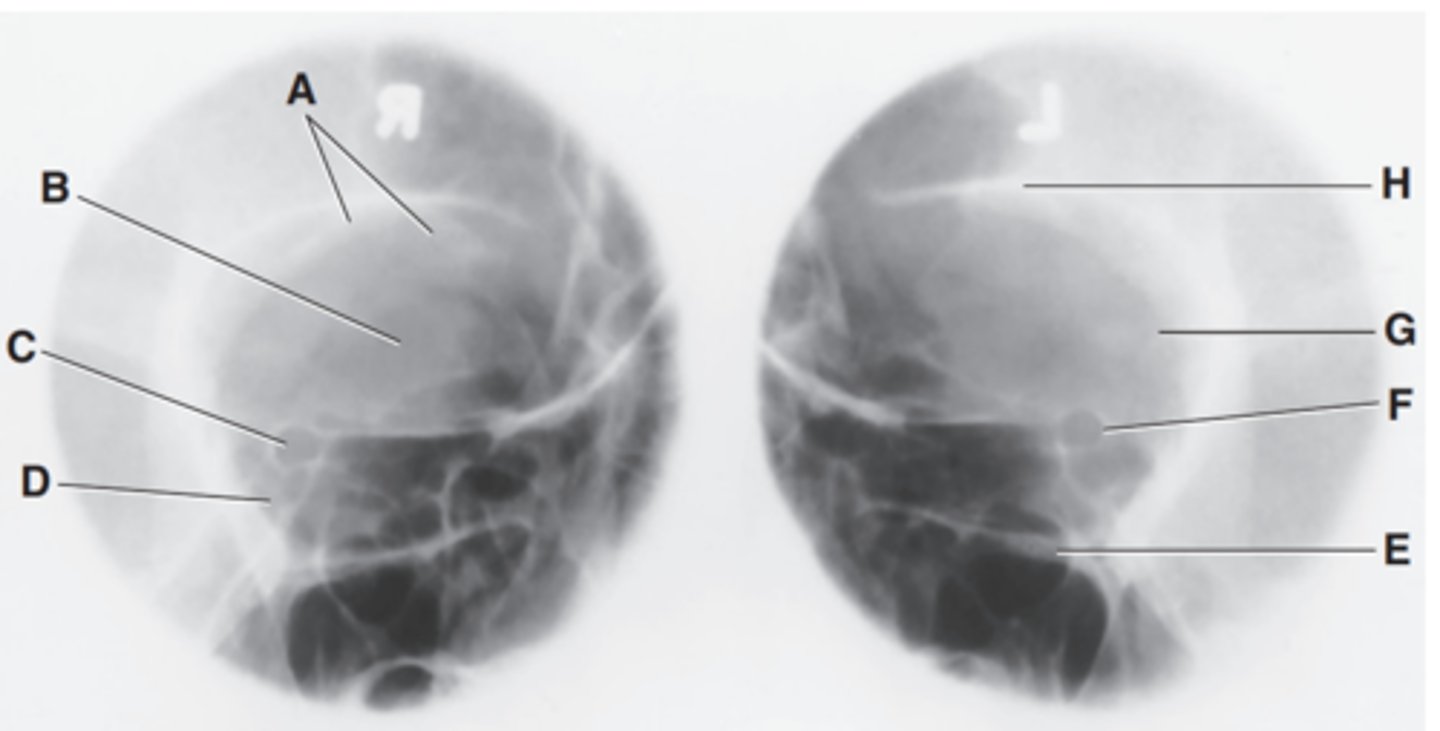

EAM

Label A

Mastoid portion of temporal bone

Label B

Occipital bone

Label C

Lambdoidal suture

Label D

Clivus

Label E

Dorsum sellae

Label F

Posterior clinoid processes

Label G

Anterior clinoid processes

Label H

Vertex of cranium

Label I

Coronal suture

Label J

Frontal bone

Label K

Orbital plates

label L

Cribriform plate

Label M

Sella turcica

Label N

Body of sphenoid (sphenoid sinus)

Label O

Petrous portion of temporal bone

Label P